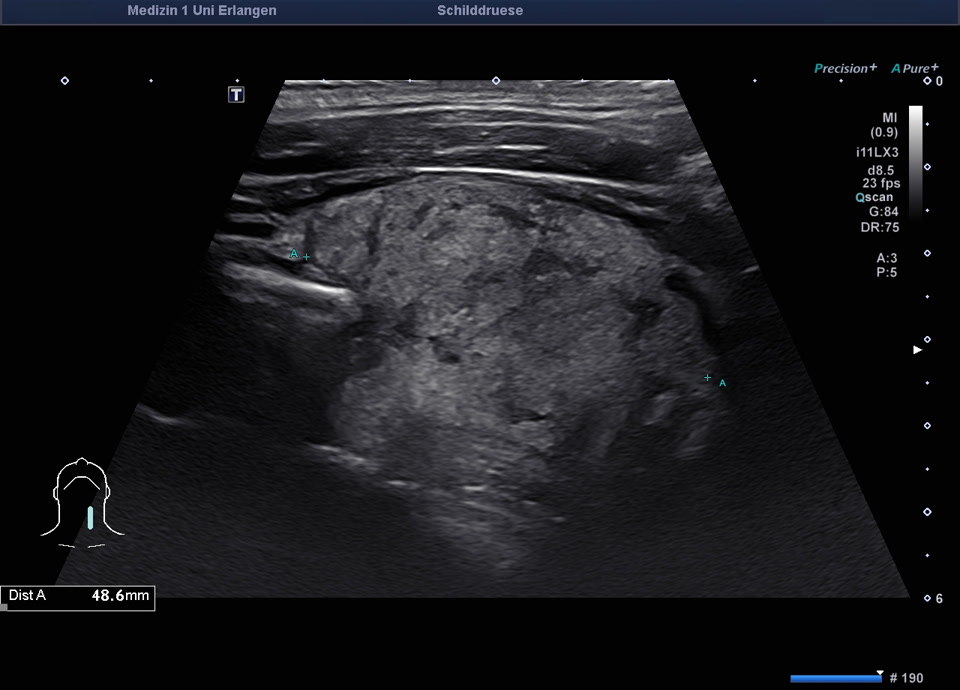

45-year-old male presented patient with persistent sore throat and general symptoms following an EBV-infection. An external diagnosis of post-infectious de Quervain’s thyroiditis had already been made, and a two-week course of corticosteroid therapy was administered. Initial clinical improvement with reduced throat pain was noted under treatment, but symptoms reoccurred after discontinuation of corticosteroids. Laboratory findings revealed leukocytosis of 12,000/µl and CRP of 113 mg/l. Sonographically, a bilaterally enlarged thyroid gland with diffusely hypoechoic areas and inhomogeneous parenchyma was observed. Combined with the patient history, this was characteristic of a subacute thyroiditis with relapse after short-term corticosteroid therapy. Prolonged corticosteroid therapy with slow tapering was performed. Under this regimen, marked clinical improvement occurred within weeks; follow-up ultrasound four months later showed a normal-sized thyroid with only mildly inhomogeneous parenchyma, consistent with resolving thyroiditis.